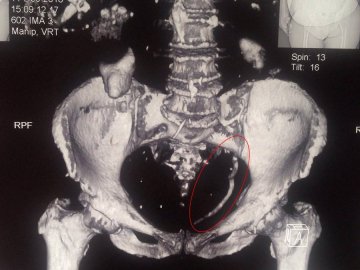

Ковельські лікарі провели контактне дроблення величезного каменю сечоводу розміром 15 см.

"Лікарями урологами Центру ендоурології ЦРЛ Ковельського МТМО успішно проведено контактне дроблення величезного каменю сечоводу розміром 15 см.", - повідомили медики.

Камінь спричинив повне блокування єдиної функціонуючої нирки, в зв’язку з чим у пацієнтки виникла важка гостра ниркова недостатність.